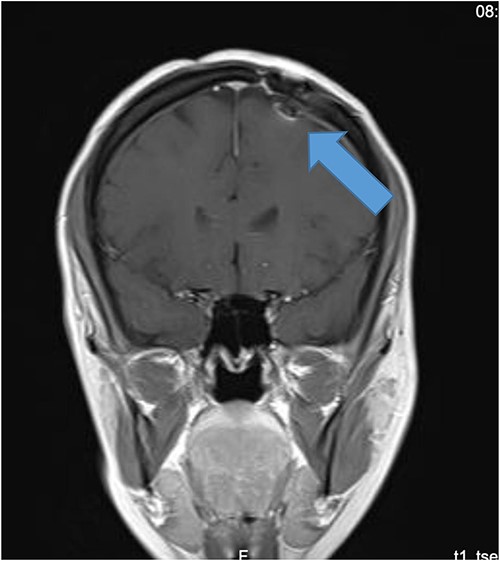

Our patient is a 31-year-old female who presented to the emergency department due to two episodes of generalized tonic colonic seizures. Upon presentation, the patient was administered with supplemental oxygen. She was drowsy and confused while exhibiting signs of right-sided hemiparesis and paralysis. Her pupils were 3 mm and reacted briskly while she showed good left-sided localizing. Her seizures terminated after intravenous administration of midazolam at 5 mg. Further, it was known that she has been symptomatic for 1 month and had been suffering from episodes of seizures, with shaking and tremors of upper limbs, and brief episodes of blackouts for about a minute. These episodes were associated with headache and nausea but were self-limited. Seizures recurred two to three times per week. She denied any fall, tongue bite, loss of consciousness, and limb weakness or numbness. A computerized tomography (CT) scan was suggested, which showed left high parietal hypodensity with vasogenic edema (Fig. 1). She was recommended Keppra 1.5 g and dexamethasone 12 mg. Further, a contrast MRI of the brain was performed (Fig. 2). After a thorough evaluation of the patient’s medical records and current condition, it was decided to proceed with an excision of the tumor using the AC technique. To foster trust and comfort, the same anesthesia and surgical teams were assigned to the patient. Before the procedure, the patient was fully informed about the nature of the procedure and the possibility of a failed outcome or further need for a conversion to general anesthesia. To assess the patient’s cognitive and language abilities, preagreed questions and exercises were performed. These included memory-related queries, such as asking for the patient’s phone number and the names of her dog, and motor commands, such as squeezing a squeaky toy. The patient was prepared for awake navigator-assisted left frontal craniotomy for excision of the left frontal lobe space-occupying lesion, which was suspected to be either a low-grade glioma or fibrous dysplasia. During the surgical procedure, a central line was placed in the right jugular vein using ultrasound, followed by the insertion of a right radial arterial line, a urinary catheter, and two additional venous lines. The patient received a continuous flow of 4–6 l of oxygen per minute. To achieve conscious sedation, the patient received infusions of remifentanil and propofol at varying rates. The patient underwent a 5-hour surgical procedure to remove a tumor. During the procedure, the patient was under sedation and was regularly tested for response to predetermined commands. Her conscious sedation level fluctuated, but she never lost consciousness. The removal of the tumor was successful, and postoperative examination revealed normal motor function and cranial nerve function. The patient was taken to the intensive care unit, and postoperative MRI showed a reduction in the size of the mass lesion in the left frontal lobe/superior frontal gyrus along with mild vasogenic edema surrounding it (Fig. 3).

MRI brain with contrast; (A) T2, (B) T1, and (C) T1 post contrast; space occupying cortical mass lesion in the left frontal lobe/superior frontal gyrus showing mild faint minimal contrast enhancement (C) (low-grade glioma).